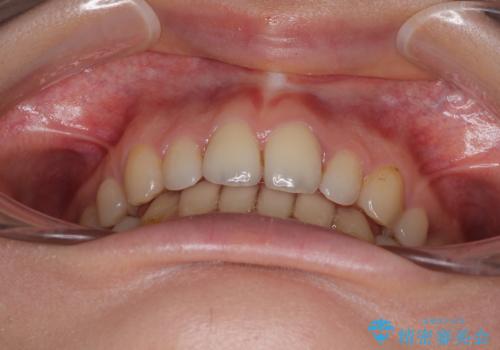

欠損や残存乳歯、深い咬み合わせ ワイヤー矯正で咬合改善

甚大な咬合力に抵抗して過蓋咬合を改善する必要があり、更には口元が引っ込みすぎることがないように仕上げていく必要もあったため、治療期間は3年を超えましたが、当初計画通りの仕上がりで治療を終えることができました。